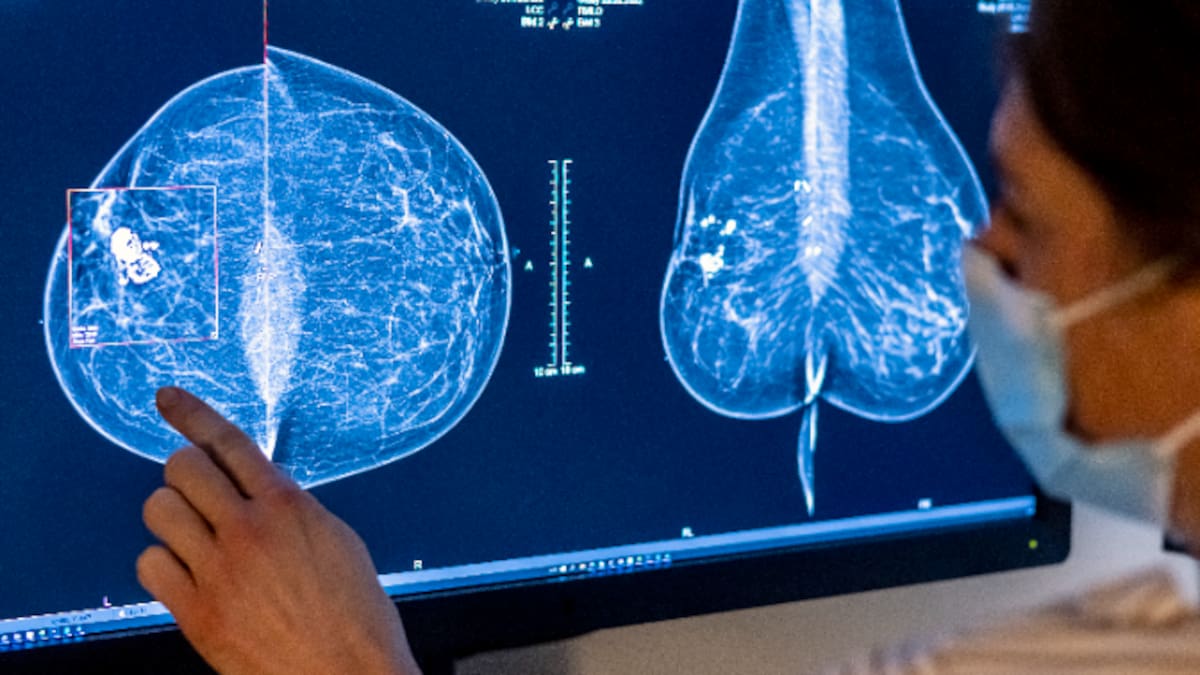

Chari y María, afectadas por los fallos en el cribado del cáncer de mama, aún no saben cuándo se operan

Afectadas por la crisis de los cribados de cáncer de mama, indignadas por las palabras de Moreno: "Estoy en lista de espera para operarme, me han dicho que de dos meses... le gritaría"

Tras cifrar el presidente de la Junta en un 1% las que han desarrollado cáncer, vuelven a movilizarse y denuncian en la Cadena SER los retrasos ahora en las intervenciones quirúrgicas